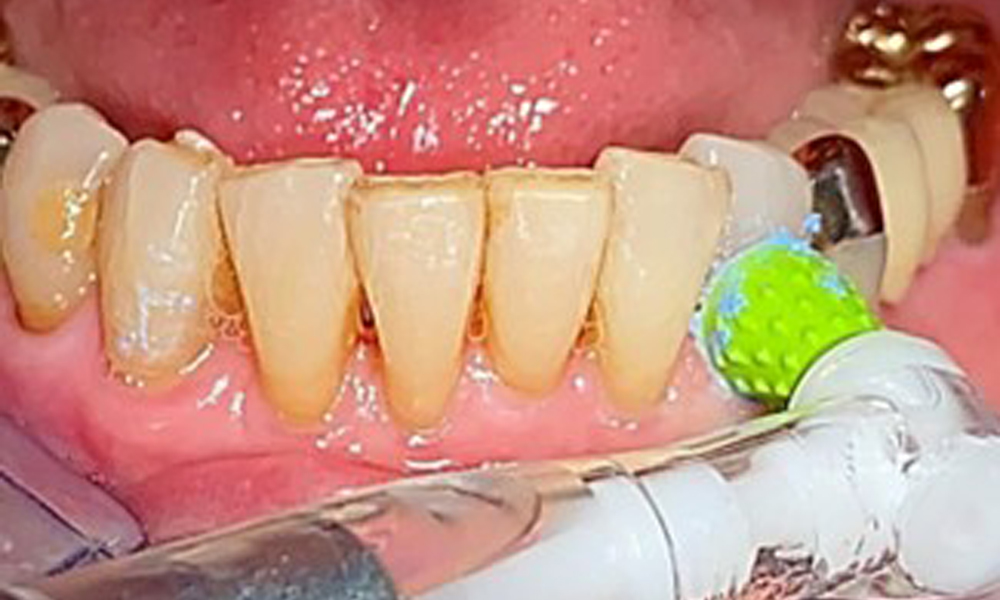

The patient was fitted with a combined removable maxillary telescopic prosthesis more than 25 years ago (Fig. 1, Fig. 2, Fig. 3) and is very happy with her dentures. The patient has an adequate fixed denture for the mandible (Fig. 4).

Frontal view with the maxillary denture in situ.

Fig. 1: Frontal view with the maxillary denture in situ.

The dental findings are as follows: Combined removable implant and tooth-supported telescopic prostheses on implants 15, 13, 21, 23, 24, 25 and tooth 11 (Fig. 1, Fig. 2, Fig. 3). The patient was fitted with a fixed mandibular denture. Adequate bridges were present over 37 to 34 and 45 to 47 (Fig. 4), the crown margins were intact and there were no active caries. A composite filling with a marginal gap was present on tooth 43. There was mandibular gingival recession, exposing 1 to 3 mm of root surface. This also applies to 11.